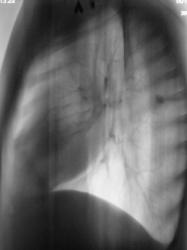

101.Rasshifrovka.JPG

Образование верхней доли левого легкого с дорожкой к корню, мне кажется может оказаться как периферическим раком ,так и туберкуломой.Надо начать с линейной томограммы. А нет ли вздутия переднего отрезка 3 ребра?

Этот дефект на всех снимках - это наше "факсимиле" - шутка. Дефект на экране, мы с ним уже смирились. Мы тоже подумали о периферическим раке и "дорожку" приняли к сведению. По поводу туберкулёза, как - то не подумали. Конечно, и о доброкачественной опухоли также вспомнили. Конечно, все "большие симпатии" в векторе периферического рака лёгкого.

А ещё смущает некоторое неоднородность, даже какие то плотные включения, межет это конечно сосуды накладываются.  Валентин Львович, у Вас же наверное где то томограмка завалялась?